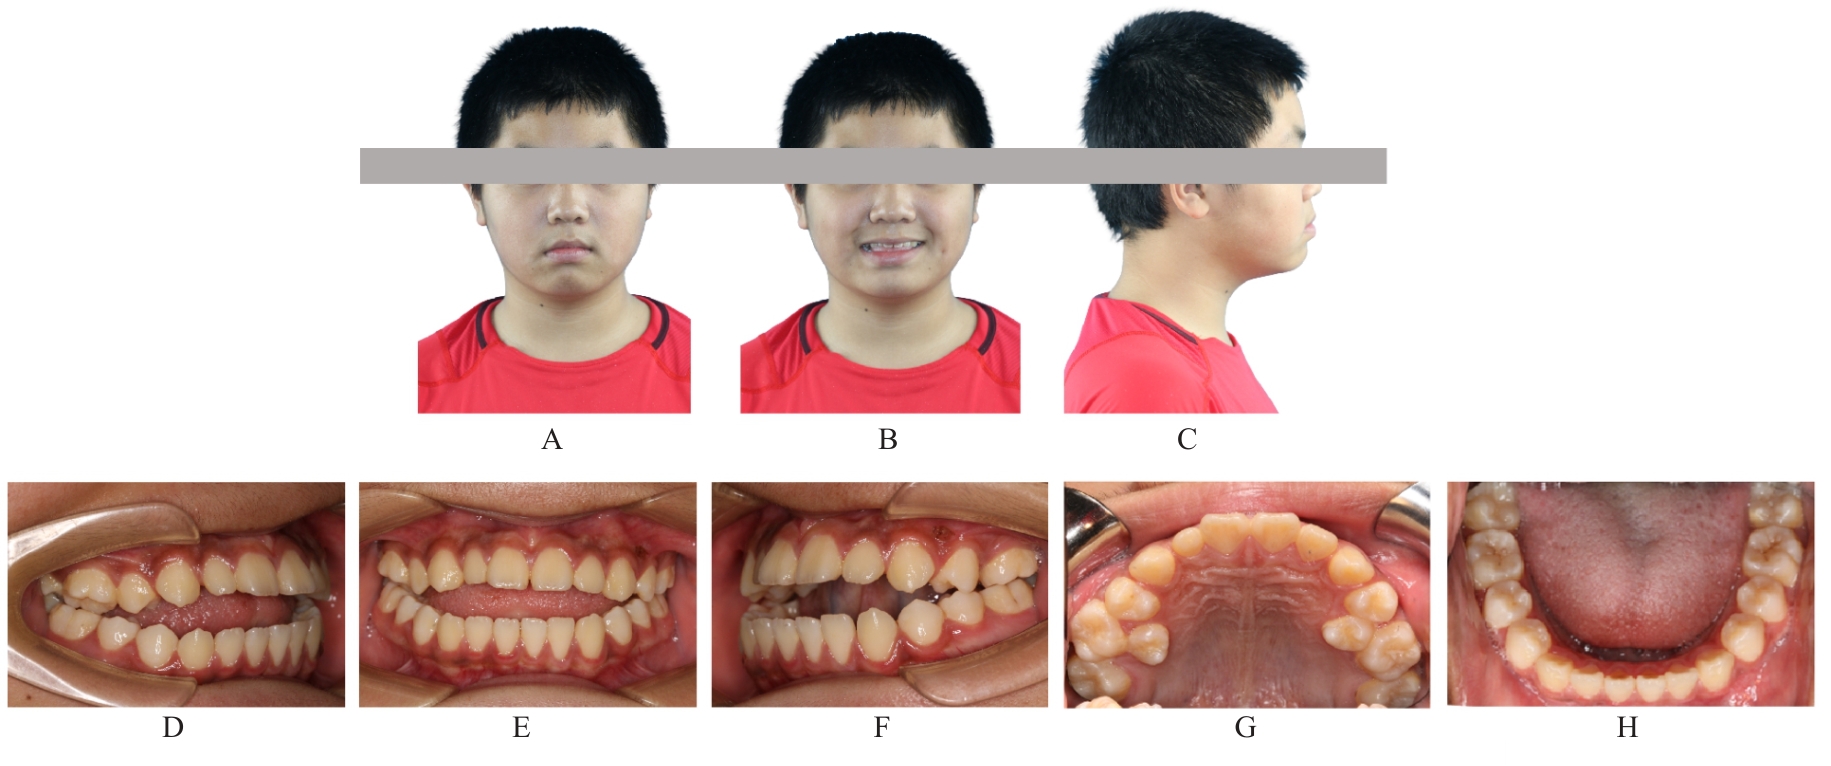

Grade Ⅲ open bite complicated with tongue hypertrophy treated by mandibular incisor extraction:A case report and literature review

Lei TIAN,Yuyan LIU,Yuqing WANG,Zhiyu ZHANG,Xiumei SUN( )

- Department of Orthodontics,Stomatology Hospital,Jilin University,Changchun 130021,China